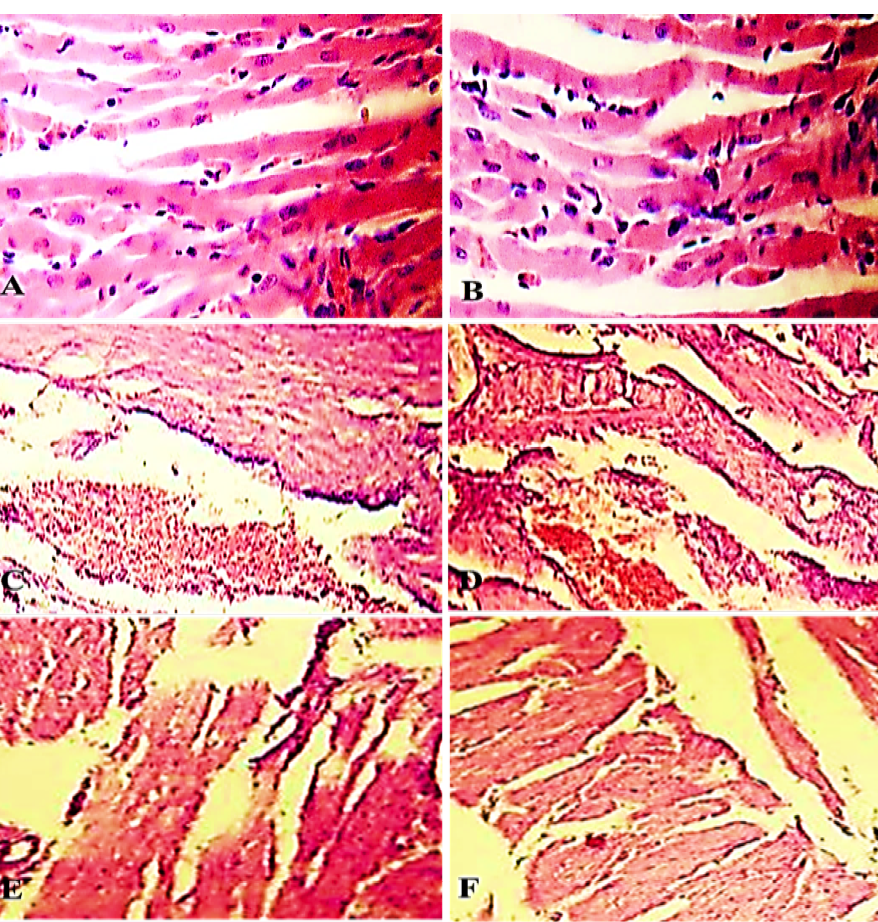

Figure 3

Heart of control group (C0h and C1h) showed normal muscle fiber run in different directions with acidophilic sarcoplasm and oval nuclei (A and B). Heart from electrocuted group (E0h) showed necrosis and intramyocardial hemorrhage (C and D). Heart of the electrocuted group (E1h) showed necrosis, fragmentation and contraction bands (E and F)